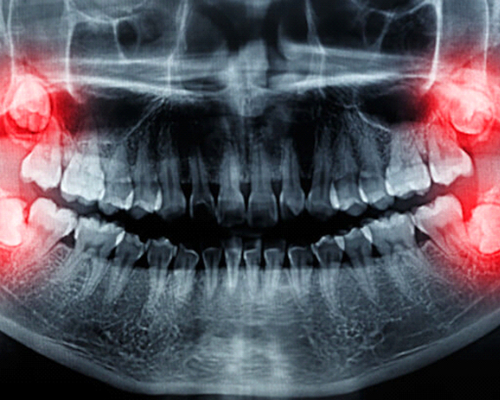

Wisdom teeth or 3rd Molars which are impacted (not fully erupted) and cause pain or difficulty in opening of mouth

Wisdom teeth or 3rd Molars are the last teeth to erupt in the oral cavity and are the last tooth present in either jaw on each side. They usually erupt any time after 18yrs of age or may never erupt.

Being the last tooth in our jaw they often do not have any space to erupt in the oral cavity and are therefore found or discovered hidden or impacted usually on an Xray

They may therefore be positioned differently and have to be examined by an OPG Xray

OPG showing 3 different 3rd molars oriented differently

OPG showing all the 4 wisdom teeth and their positions

The impacted that is not fully erupted third molars have to be extracted surgically. Under local anesthesia the bone and the soft tissue that is hindering its eruption are removed and then extraction is carried out followed by sutures